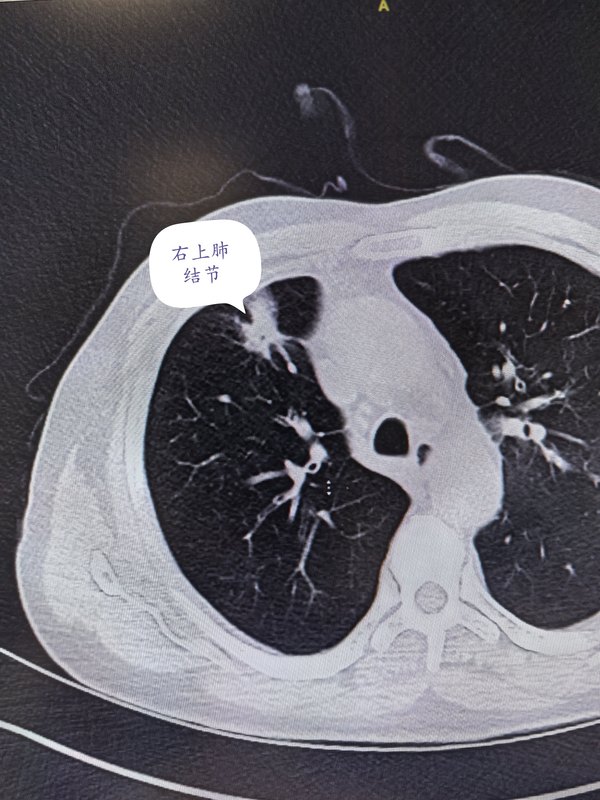

78歲老年患者在當地體檢發(fā)現右上肺結節(jié),考慮炎癥可能。經消炎二周治療無效。至我院行微創(chuàng)單孔胸腔鏡手術治療。手術順利,術中病理提示浸潤性腺癌,行右上肺切除+淋巴結清掃。術后病理證實淋巴結無轉移,胸膜無侵犯。雖然結節(jié)證實是肺惡性腫瘤,但是屬于早期,每年定期隨訪觀察即可,無需后期化療等治療,在高齡患者中是比較好的結果。